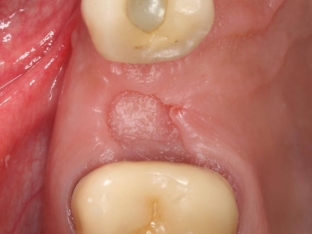

At the site of the extracted tooth, instead of a blood clot, a bone is visualized, and the hole itself looks dry.

About 2 days after the extraction of the tooth, acute pain appears, which intensifies and radiates to the ears. Others notice bad breath, and the patient notices a change in taste sensations.